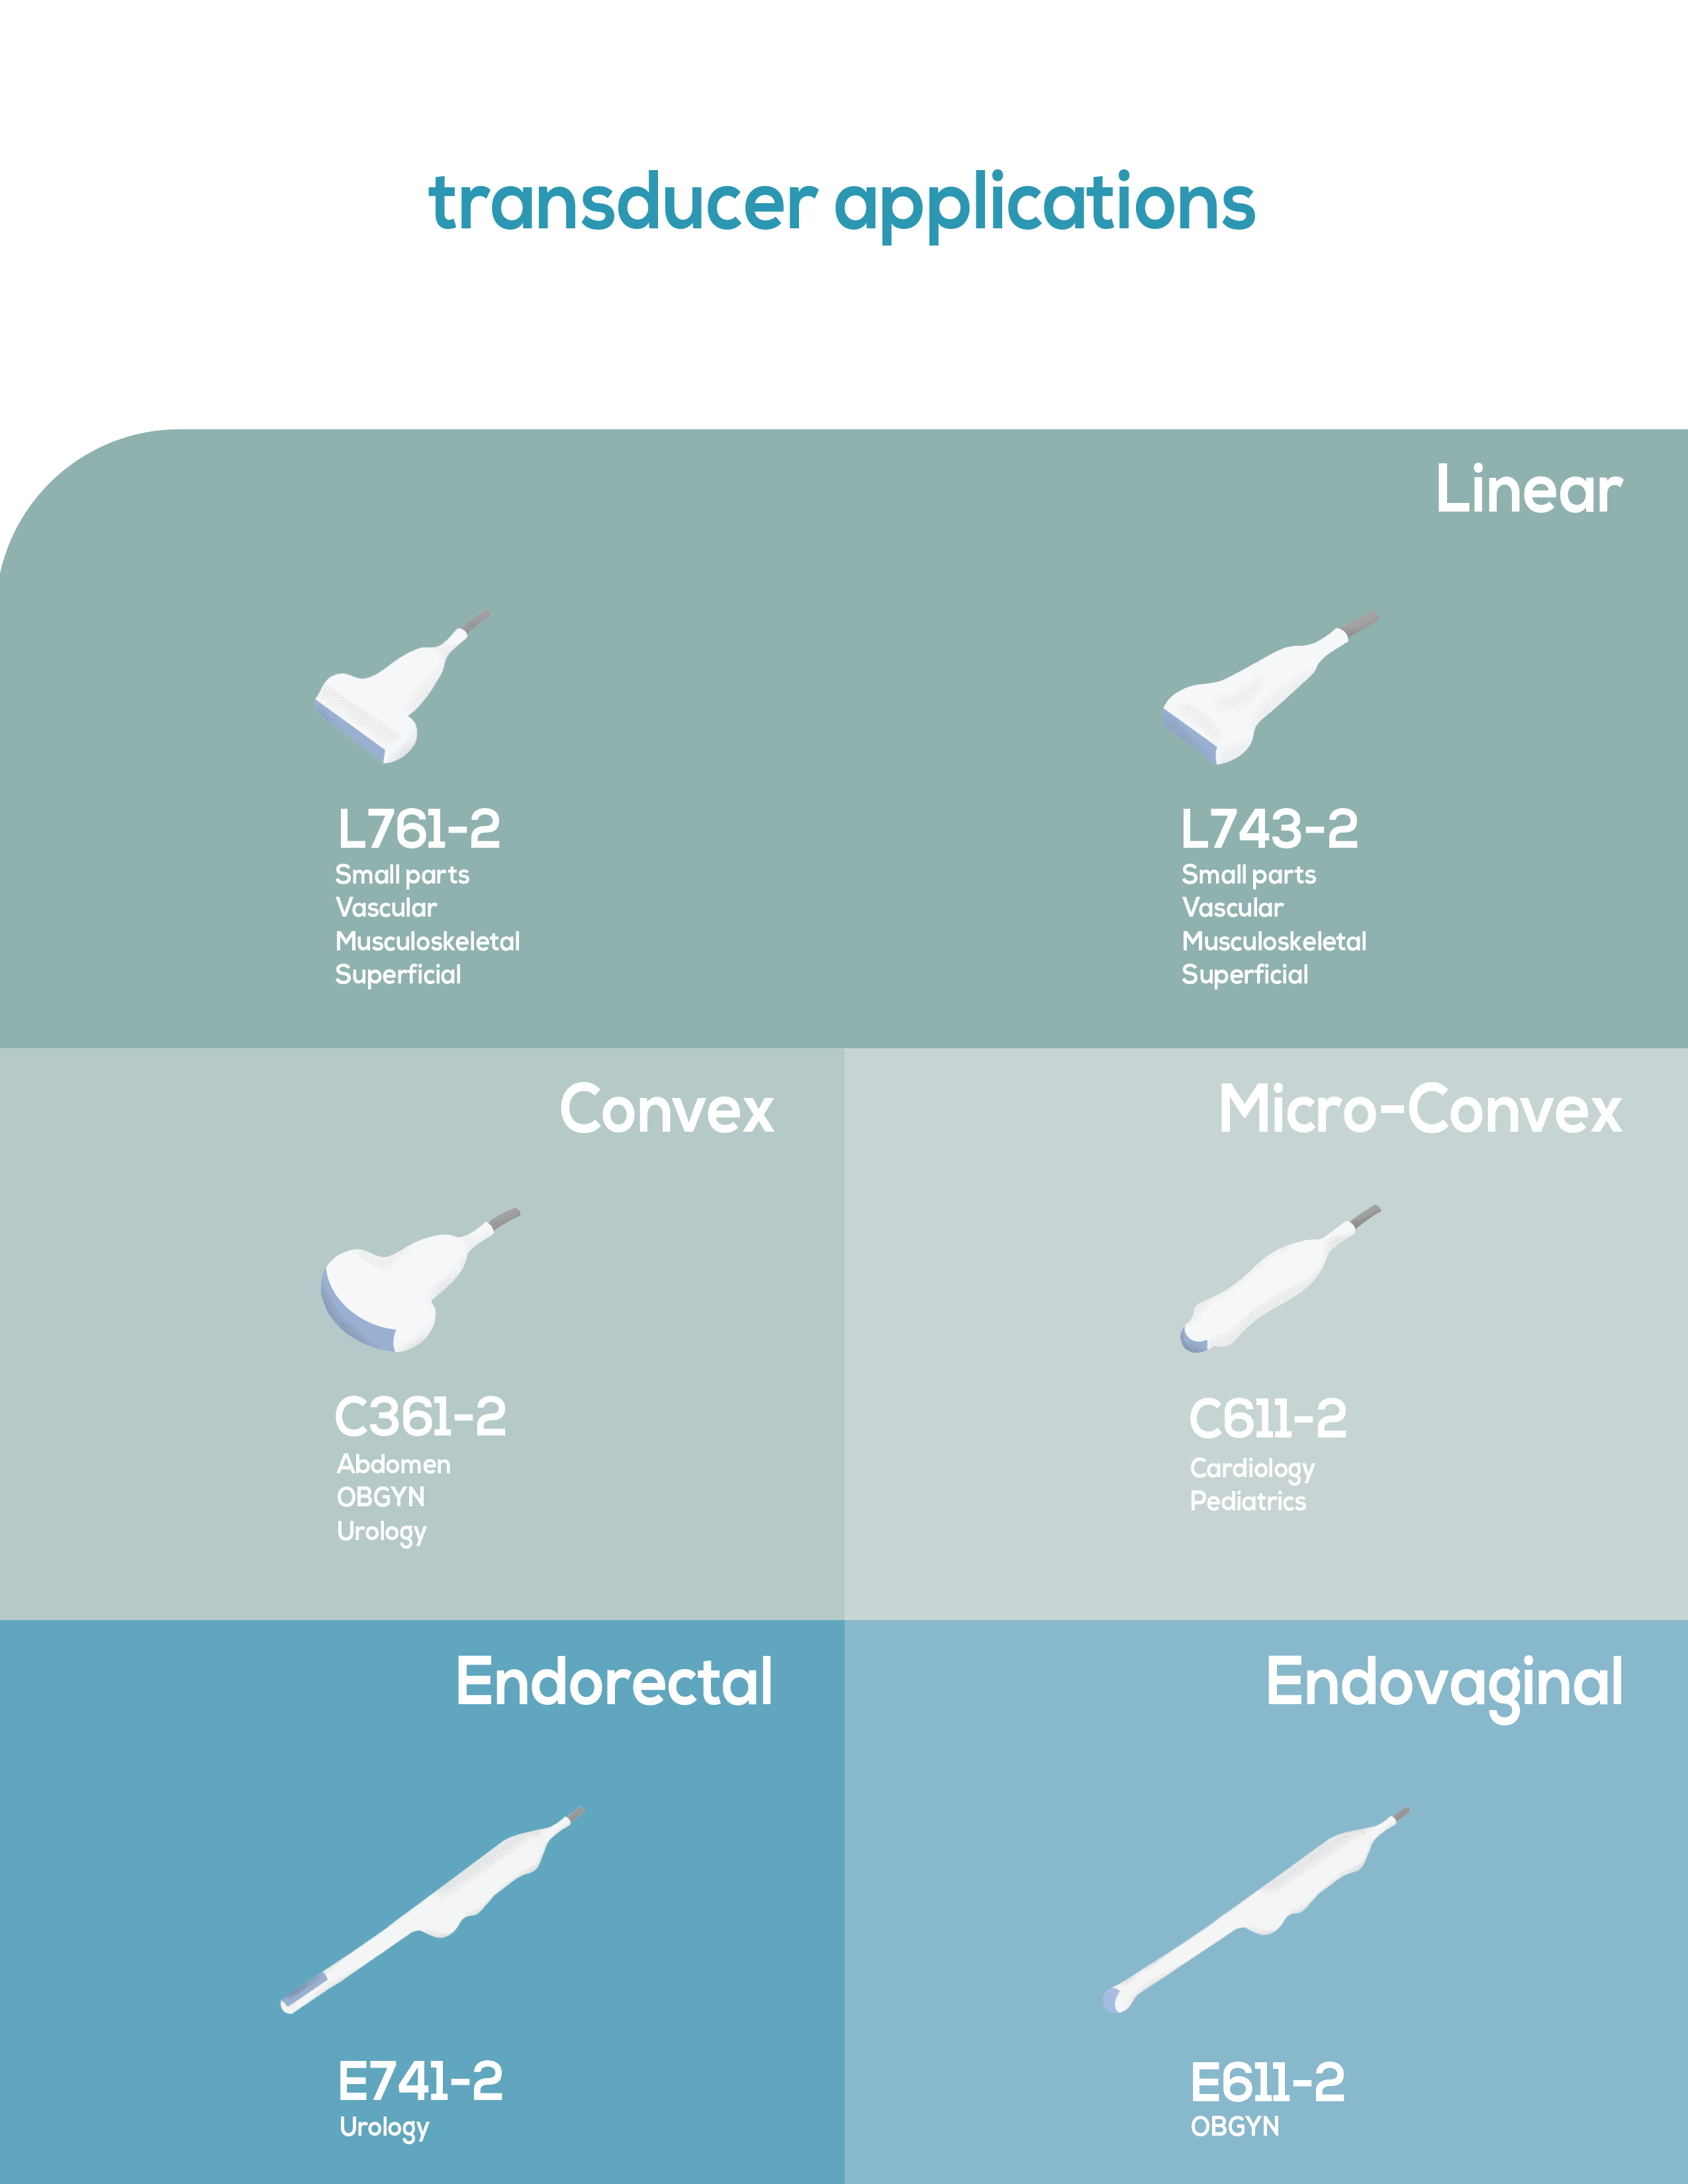

Five-frequency transducers increase versatility

Canine, Feline, Bovine, Equine, Ovine,

Abdomen, Obstetrics, Small Parts, Vascular, MSK, Cardiac